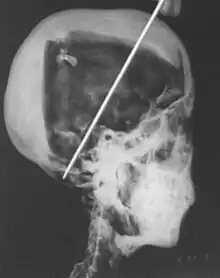

In 1968 R. G. Harrison, a professor of anatomy, used a portable x-ray machine to re-examine the mummy of Tutankhamun. Harrison quickly discovered that Carter had dismembered the mummy, something that is not mentioned in his publication. The mummy, surrounded by cotton wool and secured by modern bandages, had deteriorated since last photographed by Carter's team in 1926. The beaded skull-cap had disappeared, as had most of the skin on the head; the eyes appeared to be wide open, and the ears were largely destroyed. The beaded collar was gone, as was the front wall of the king's chest; stray beads from this necklace were seen scattered in the torso on the x-rays. The limbs had been moved and further disarticulated, with the left hand and thumb of the right hand found in the sand under the body.[80][81] Although not mentioned by Harrison, the king's penis was also missing.[81] The additional damage to the mummy and the removal of the skullcap and collar likely occurred during World War II,[60] and components suggested to be from the collar have since appeared on the antiquities market.[82]

The x-rays revealed two levels of resin inside the skull. One was introduced when the body was lying on its back, pooling at the back of the head; the other when the head was tilted far back, settling at the top of the skull. Also present in the skull cavity were small bone fragments which Harrison initially believed to be the result of the embalming process. The fact that skull fragments were discovered led many to assume the king was murdered by a blow to the head, but the X-ray could not support or discredit this theory. His age at death was again estimated to be around 18, with a projected height in life of 168.9 centimetres (5 ft 6.5 in).[80] Serological analysis undertaken by the same team determined that Tutankhamun and the KV55 mummy had the same blood group, further indicating a familial relationship.[83]